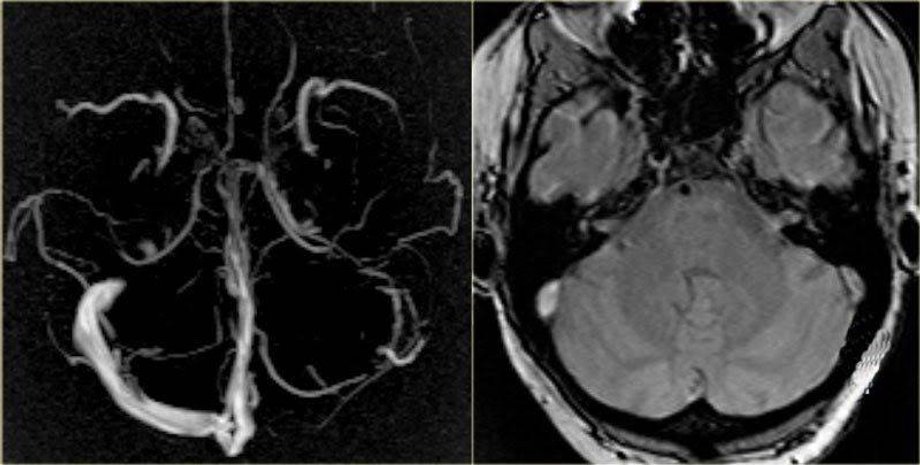

Тромб в мозгу на МРТ | Фото: "Магнит"